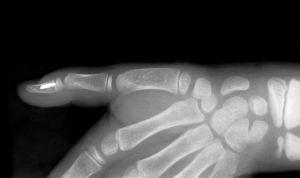

JUST A QUICK NOTE THIS TIME I am typing one handed right now, having stumbled in the gym this morning only to drop a loaded barbell (85 pounds) on my left hand. (At least it wasn't my right!) Two broken fingers with one bone on the end of one finger crushed. So enjoy the newsletter. (Thank God I prepared it a couple days ago.) (PS - Not my hand below. You don't want to see the real one.) |